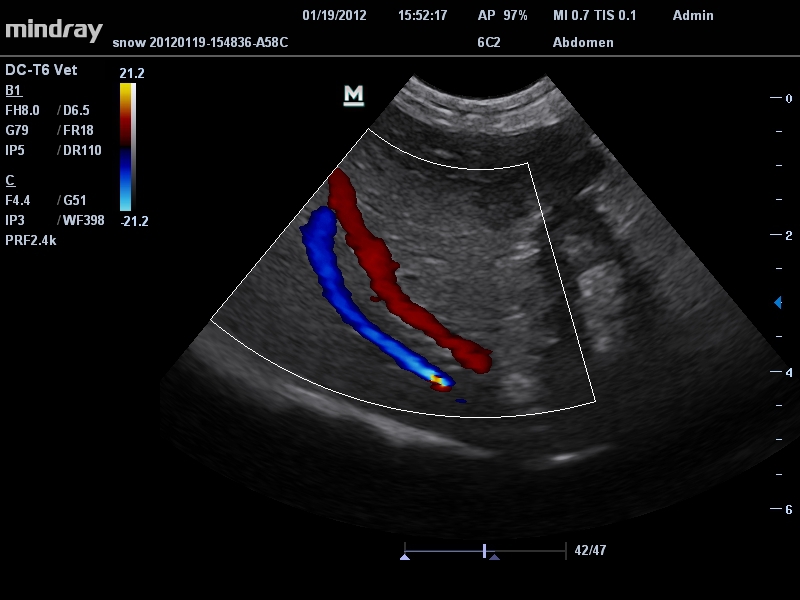

Mindray DC-T6

Ультразвуковая система Mindray DC-T6 – это инновационный аппарат для проведения высокого уровня диагностики с качественной визуализацией и широким спектром применения. Платформа рекомендована для использования в коммерчески многопрофильных медицинских учреждениях и государственных лечебных клиниках.

Цветовой допплер:

Да

• IMT: автоматический расчет толщины интима-медиа сосудов.

• Микроконвексный датчик Mindray 6C2